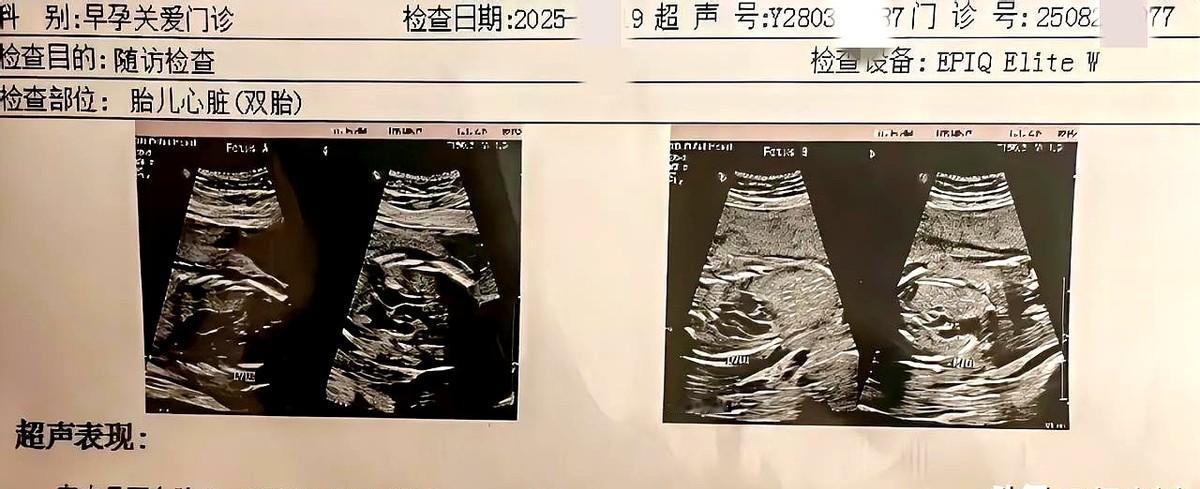

太意外了我老婆怀了双胞胎!这次真的是意外怀孕了,我老婆已经44岁了,还是双胞胎